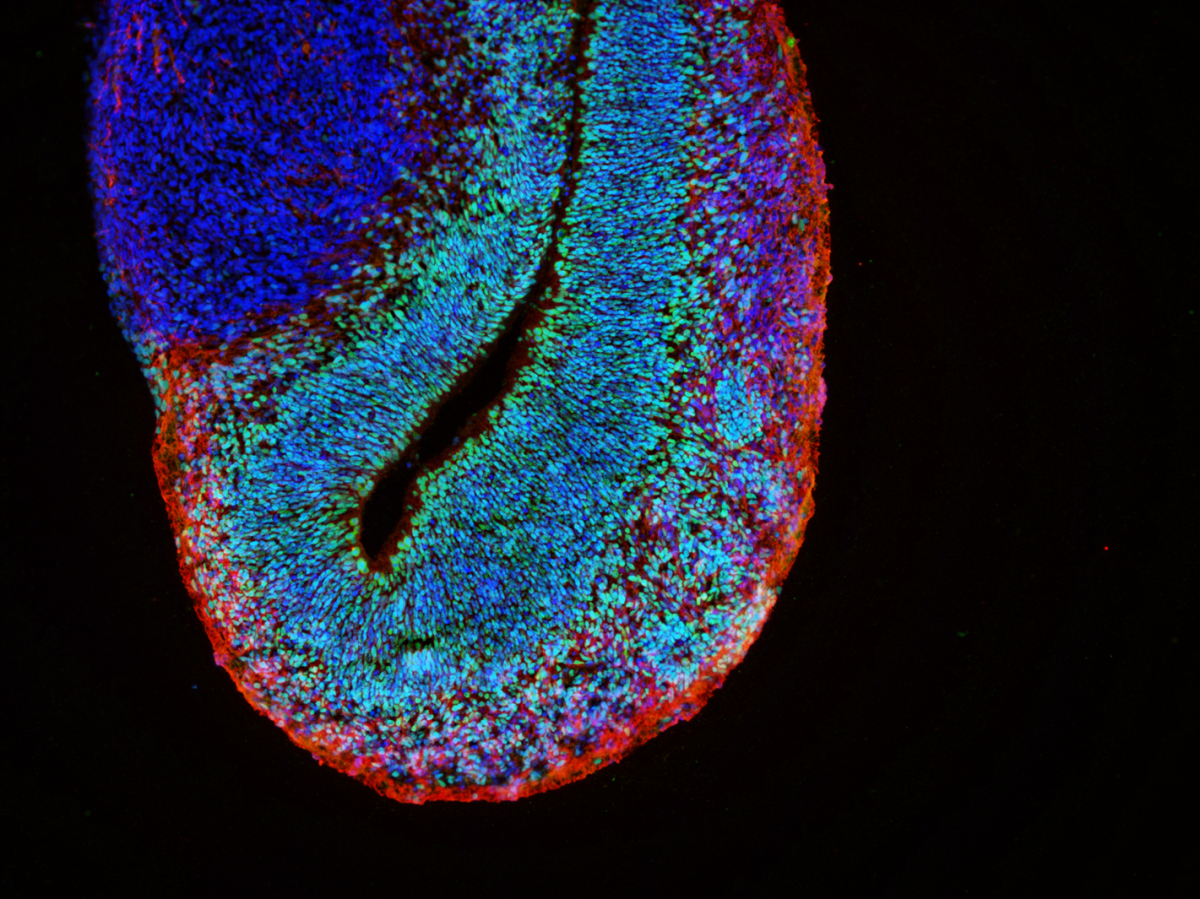

Alexandrova choroba je způsobena mutací genu GFAP, který kóduje gliální fibrilární kyselý protein. Tento protein je produkován zejména v astrocytech, buňkách, které podporují správnou funkci neuronů. Z tohoto důvodu je také Alexandrova choroba chápana jako primární onemocnění astrocytů, ačkoliv vliv dalších buněk nervové soustavy nebyl zcela vyloučen. Mutace genu GFAP způsobuje změnu vlastností vznikajícího proteinu. Jedním z důsledků je pak tvorba proteinových shluků, tzv. Rosenthalových vláken, uvnitř astrocytů. Tyto shluky se staly také prvním klíčovým identifikátorem při diagnostice Alexandrovy choroby v začátcích jejího studia. Změněná exprese genu GFAP pravděpodobně přispívá k aktivaci astrocytů a dalších buněk nervového systému, což vede k zánětu a konečné ztrátě bílé hmoty. Nicméně přesné mechanismy a zapojení jednotlivých buněčných typů zatím nejsou známy.